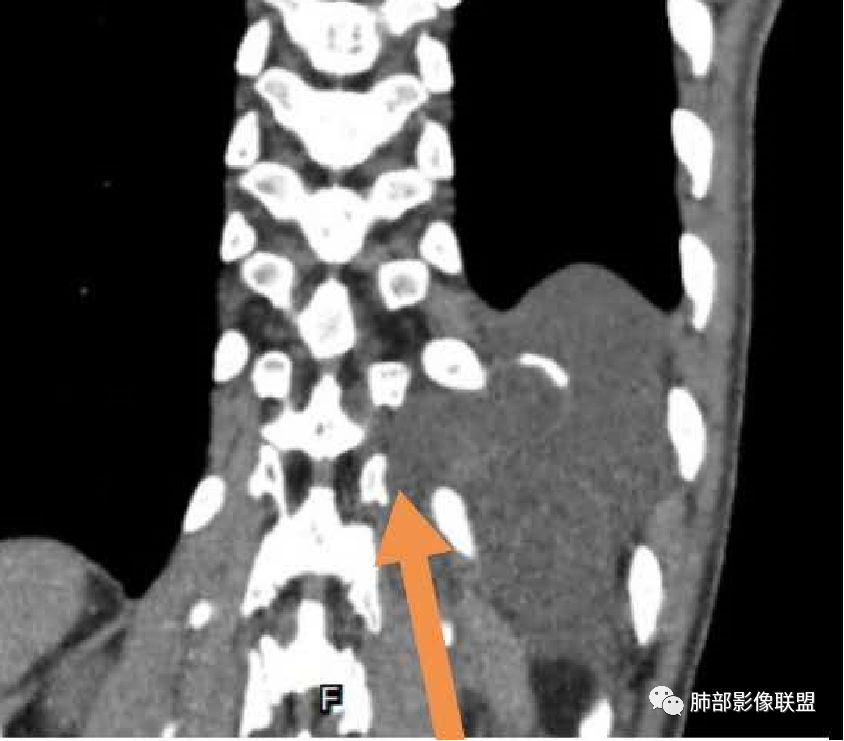

首先需要定位在哪?纵隔?胸壁?

应该是跨区域了。跨区域一般我们的分析:

1、病灶由一侧突入到另外一侧。

2、两个区域病灶融合,这一例好像符合后者。

现在我们重新回顾性分析这个病例的影像特点:

1.含有少量脂肪密度成分,位于病灶中央区,应当是病灶内的一部分,或者说至少这部分不是被包绕卷入的。常见病灶内含有脂肪组织的肿瘤:多种脂肪瘤、脂肪肉瘤、畸胎瘤、其他肿瘤伴脂肪化生或分化。

2.病灶中间弧形稍高密度影,提示纤维组织可能,而且很有张力并呈分叶状,伴弧形钙化,提示这个倾向于病灶的包膜。